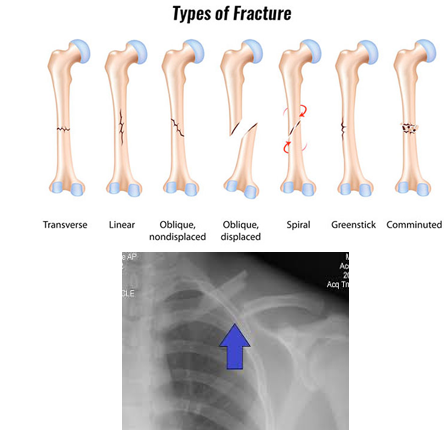

Common Pediatric Fractures

Greenstick

Buckle

Compound or Open

Stress Fracture

Spiral Fracture

Greenstick Fracture

Incomplete fracture

That thick periosteum comes into play!

Buckle Fracture

Raised or bulging projection at the site

Seen in the wrist, typically from a fall on an outstretched hand (FOOSH).

Compound or Open Fracture

Fractured bone protrudes through the skin

It can be just a little bit or a lot.

Patient is at a huge risk for infection of the bone and their body.

Stress Fracture

Tiny cracks in a bone

Seen in athletes.

Spiral Fracture

Spiral appearance of fracture

Always investigate spiral fractures in children when the mechanism of injury does not match the fracture type, especially in a non-ambulatory child!

It takes a great force to cause this injury.